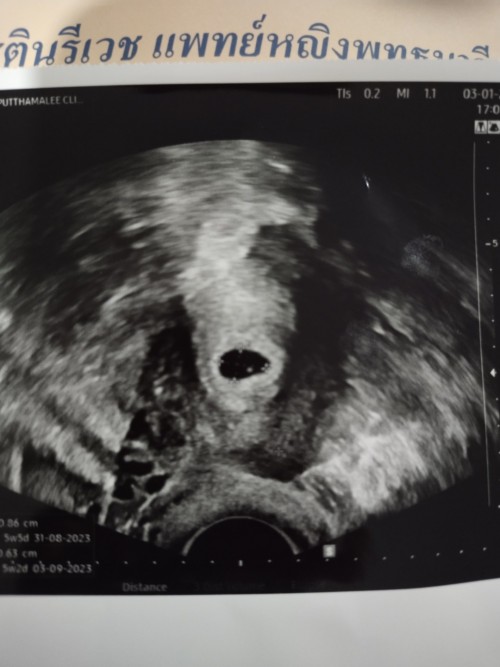

บ้านนี้เห็นแค่ถุงตั้งครรภ์ค่ะป้าหมอนีดอีกที่วันที่18มกรานี้ค่ะสู้ๆนะคะคุณแม่😊😊

5-6w แล้วค่ะ น้องมีหัวใจคุณแม่ได้ยินเสียงหัวใจน้องแล้วน้ำตาไหลเลย 🥰🥰

เราเห็นแค่ถุงตั้งครรภ์ค่ะ นัดอีกทีเดือนหน้า

ของบ้านนี้ตอน 5w เห็นแค่ถุงตั้งครรภ์ค่ะ

ท้อง 5 week เจอน้องค่ะแต่หัวใจยังไม่เต้นค่ะ

น้องจิ๋ว 5 week ค่ะ

5 w